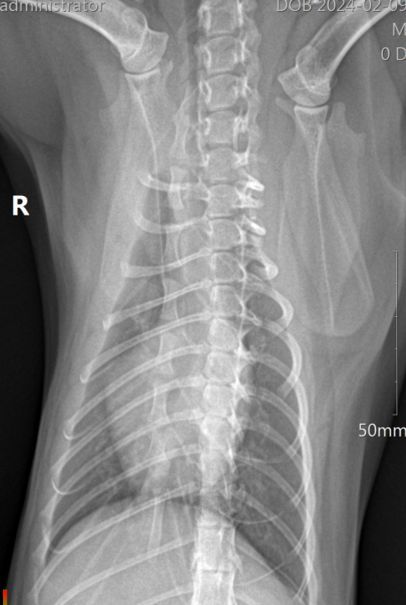

以下为外院提供的X线片,从X线片可见胸腔整体不投射性增加,心影轮廓不清,心脏增大,正位心脏呈”情人心“;肺前动静脉扩张,前腹侧和后腹侧可见混合肺泡型,怀疑肺炎、肺水肿、肺出血等;心脏略增大、心尖钝圆,需结合超声心动图诊断。

4.2.5 胸腔X线光(2.09)

结果提示:X线片可见肺水肿已经明显改善。